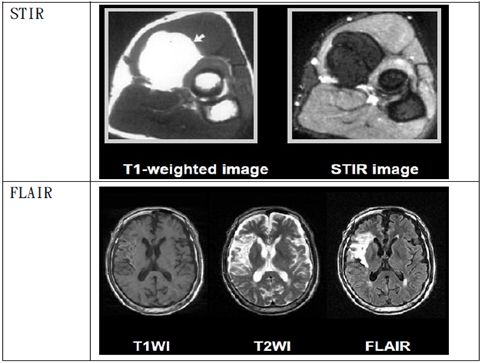

STIR─ Short TI inversionnRecovery(短TI反轉回復):

利用RF加在X軸,使磁矩在Z軸直接反轉,並等待組織成份進行recovery,通過“null point”之後才開始造影。例如;抑制脂肪,就等脂肪通過null point再開始造影。然而在90°RF 脈衝之前先給予180°RF脈衝,這段時間稱之TI(inversion time)。脂肪屬於短TI,適當設定TI,即可抑制脂肪訊號,因此在影像上會是暗訊號。同理當抑制對象是水時,此方式稱“FLAIR─fluid attenuatedninversion recovery(流體稀釋反轉回復)。